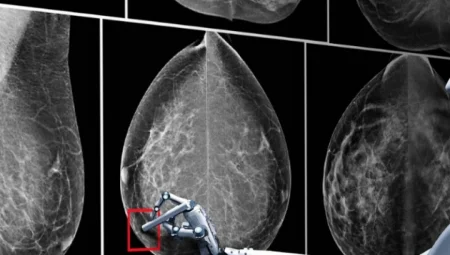

Sağlık sektöründe yapay zekâ (YZ) destekli uygulamalar giderek yaygınlaşıyor. Özellikle kanser ve genetik hastalıkların teşhis…